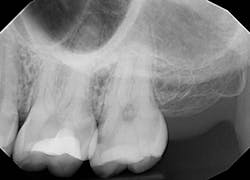

Restoring the proximal wall initially allows more time for the dentin bond to mature before adding subsequent dentin replacement layers, thus lessening polymerization stress. Preoperative radiographs of the affected tooth were taken, confirming deep initial decay on tooth no. 15 (figure 1). An ideal restorative environment and isolation were achieved with a rubber dam. A light blue Isodam (Four D) was utilized, which provides better visual clarity and light reflection. The Isodam was anchored with a W8A clamp (Hu-Friedy) for better restorative access when placing sectional matrices after cavity preparationNext, a sectional matrix (Garrison Dental) was placed and burnished with a spoon to facilitate a broad adaptation of the band to the adjacent tooth (figure 4). A Palodent V3 ring (Dentsply Sirona) was placed for separation and to ensure a tight resultant contact.